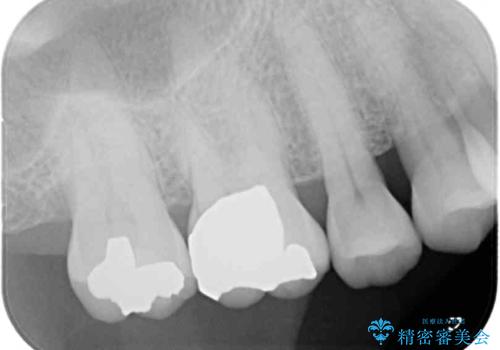

ゴールドインレーは銀歯のインレーやセラミックインレーと比べ、「技工操作の精度が高く、適合が著しく良い」というメリットがあります。特に上の奥歯は歯科医師の操作が行いにくいため、「適合の良さ」は再治療のリスクを防ぐ上でとても重要な要素となります。

上の奥歯は金属色が見えることもないため、審美的な問題は全くありません。

咬み心地はとても良好で、全く違和感がなく、患者様には大変満足していただきました。